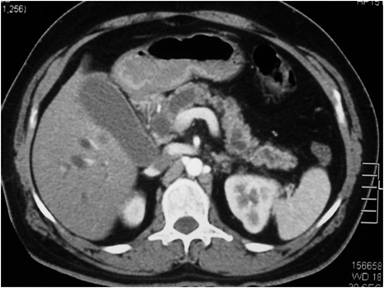

A previously well 24-year-old male presented with a one month history of rapidly progressive obstructive jaundice associated with abdominal pain suggestive of a biliary colic. He was otherwise well except for anorexia of the same duration. His past medical and family history were unremarkable except for receiving treatment for meningitis two years back. General examination revealed he was deeply icteric, but free of supraclavicular lymphadenopathy and features of chronic liver disease. Abdominal examination showed tender hepatomegaly with a palpable gallbladder but no free fluid. His liver functions were deranged with significantly elevated serum bilirubin and alkaline phosphatase levels. Trans-abdominal ultrasonography showed a suspicious pancreatic head mass, a dilated common bile duct (1.8 cm) and a distended gallbladder with no calculi. Contrast-enhanced CT (CECT) of the abdomen revealed a pancreatic head mass encircling the main pancreatic duct and CBD opening. Tumor also extending into the duodenal wall through muscularis propria without evidence of superior mesenteric or portal vessel involvement nor distal metastases. The pancreatic duct showed significant dilatation but there was no intraductal parenchymal calcification (Figures 1 and 2). These findings were corroborated by upper gastrointestinal endosonography. Pre-operative ERCP and stenting was done for nutritional optimization prior to surgery. Based on a preoperative diagnosis of an ampullary malignant stricture a standard pancreaticoduodenectomy (Whipple’s procedure) was performed. During surgery, the entire pancreas was found to exhibit a hard texture but there was no evidence of peritoneal or liver metastases. Postoperative recovery was uneventful except for a minor (ISGPF – grade A) pancreatic fistula which resolved with conservative management. The resected specimen (Figure 3) showed an irregular, solid, whitish mass measuring 4.4x3.0x3.0 cm. Histology demonstrated a lesion composed of nests of small round cells with scanty cytoplasm surrounded by prominent desmoplastic stroma, compatible with a poorly differentiated DSRCT of the pancreatic head (Figure 4). The resection margin was positive and there was perineural and vascular invasion. The tumor cells were negative for synaptophysin and chromogranin but positive for desmin and cytokeratin (Figure 5). Peripancreatic lymph nodes were positive for the tumor deposits. He received adjuvant combination chemotherapy that included vincristine, cyclophosphamide, doxorubicin, ifosfamide and etoposide. Clinical assessment and CECT done six months after surgery showed him to be well with no evidence of disease progression.

Figure 2. CECT abdomen showing pancreatic head mass with dilated main pancreatic duct. |